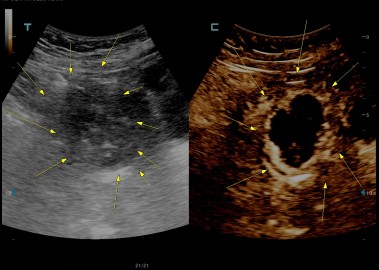

다발성 자궁근종 치료 사례